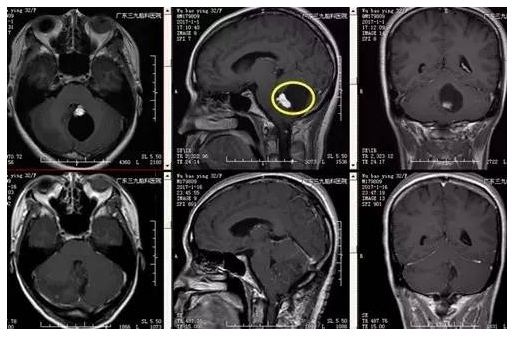

伍某某,32岁,发现颅内占位病变2年,行走不稳1天,为求进一步治疗,来我院就诊。入院后完善相关检查后,术前CTA提示实体病变,血供异常丰富,术前MR提示肿瘤位于桥臂背侧,行小脑血管母细胞瘤切除术,手术由神经外一科主任张良主刀完成,术程顺利,术后病变全切除,术后病理提示血管母细胞瘤(WHO I级),目前恢复良好。

▲术前MR

广东三九脑科医院神经外一科张良主任介绍:血管母细胞瘤是由脑神经和脊髓神经所产生的一种高度血管分化的良性肿瘤。大多数的血管母细胞瘤是由单一病灶所产生的。血管母细胞瘤起源于中胚层细胞的胚胎残余组织,为富含血管的良性肿瘤,多好发于后颅窝,占颅内肿瘤的1.5%-2%,占后颅窝肿瘤的7%-12%。约70%的血管母细胞瘤为囊性,好发于30-40岁,男性稍多于女性,部分有家族史,大多以颅内压增高及小脑症状而就诊,常以头痛为首发症状,逐渐出现呕吐、视物模糊、复视及视力下降,如合并脑积水则症状加重明显,部分患者以小脑症状为主要表现,主要为眼球震颤和共济失调。本例患者为32岁女性,以共济失调为主要表现就诊,MR见大囊小结节病灶,结节增强后明显强化。